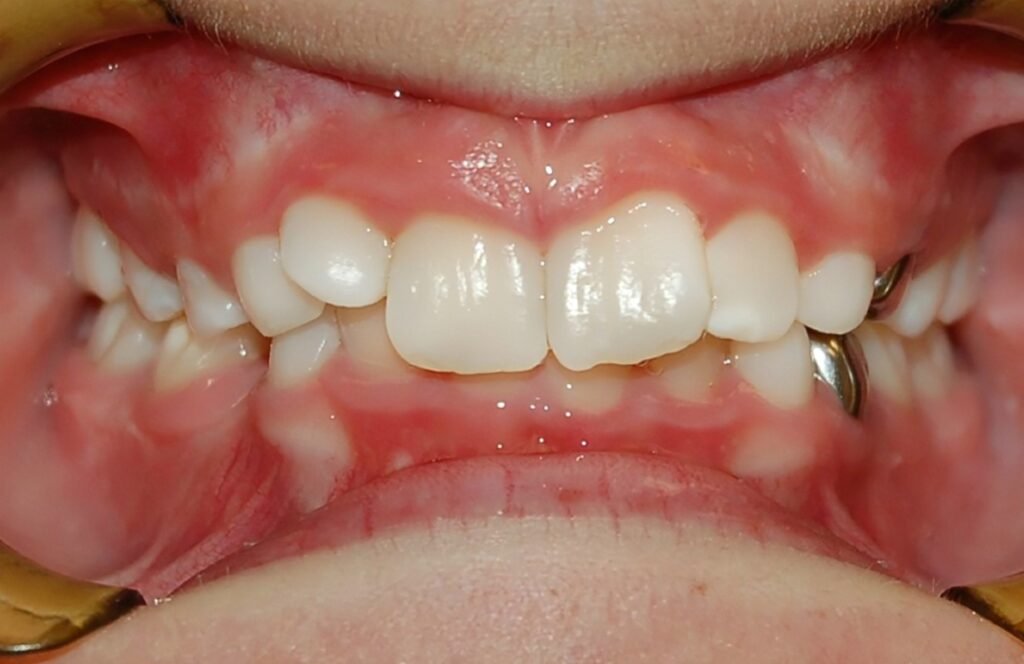

Anterior Open Bite

Clinical Presentation: Inability of the front teeth to make contact when the back teeth are closed.

Zebris Findings: Anterior segment showing no contact during occlusion, leading to compensatory movements in the jaw and TMJ strain.